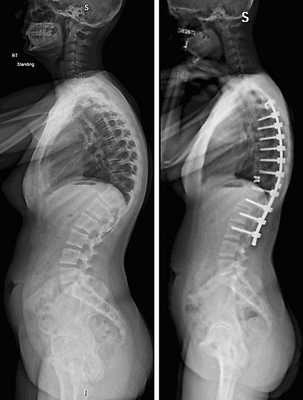

Коррекция кифоза грудного отдела.

Показаниями к вживлению ригидных конструкций транспедикулярной фиксации, в том числе и Krypton®, служат практически все случаи позвоночной нестабильности:

- выраженный листез позвонков;

- травмы позвоночника (вывихи, переломы и пр.);

- спинальные новообразования;

- дегенеративные патологии, сопровождающиеся неврологическим дефицитом, например, межпозвоночные поясничные грыжи; и кифоз;

- несостоявшийся артродез;

- последствия неудачно выполненных вмешательств и др.

При правильном проведении техника обеспечивает ярко-выраженные положительные результаты лечения в подавляющем большинстве ситуаций. С ее помощью возможно частичное или даже абсолютное восстановление функциональной способности позвоночника после перенесения серьезных травм, приведших к параличу. Она же позволяет устранить болевой синдром, сопровождающий заболевания, включая сколиоз.